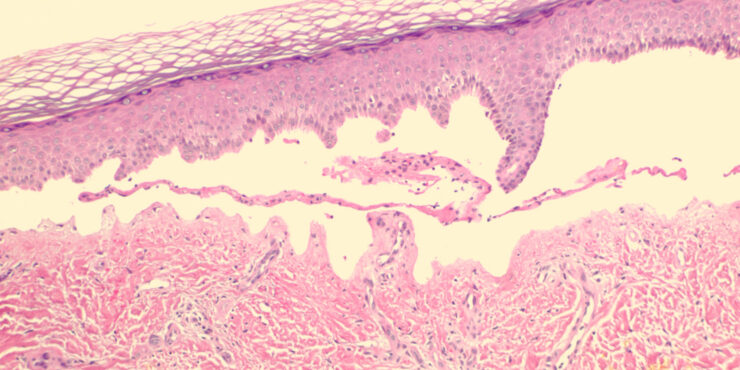

Poroma=شزن=تورم بسبب إفراز غدي POROMA The term poroma refers to a group of rare cutaneous appendage tumors composed of cells (cuticular and poroid cells) similar to those of the acrosyringium. Poromas are traditionally subcategorized histopathologically based on their location in relation to the epidermis into three main variants; namely, hidroacanthoma simplex, eccrine poroma, and […]